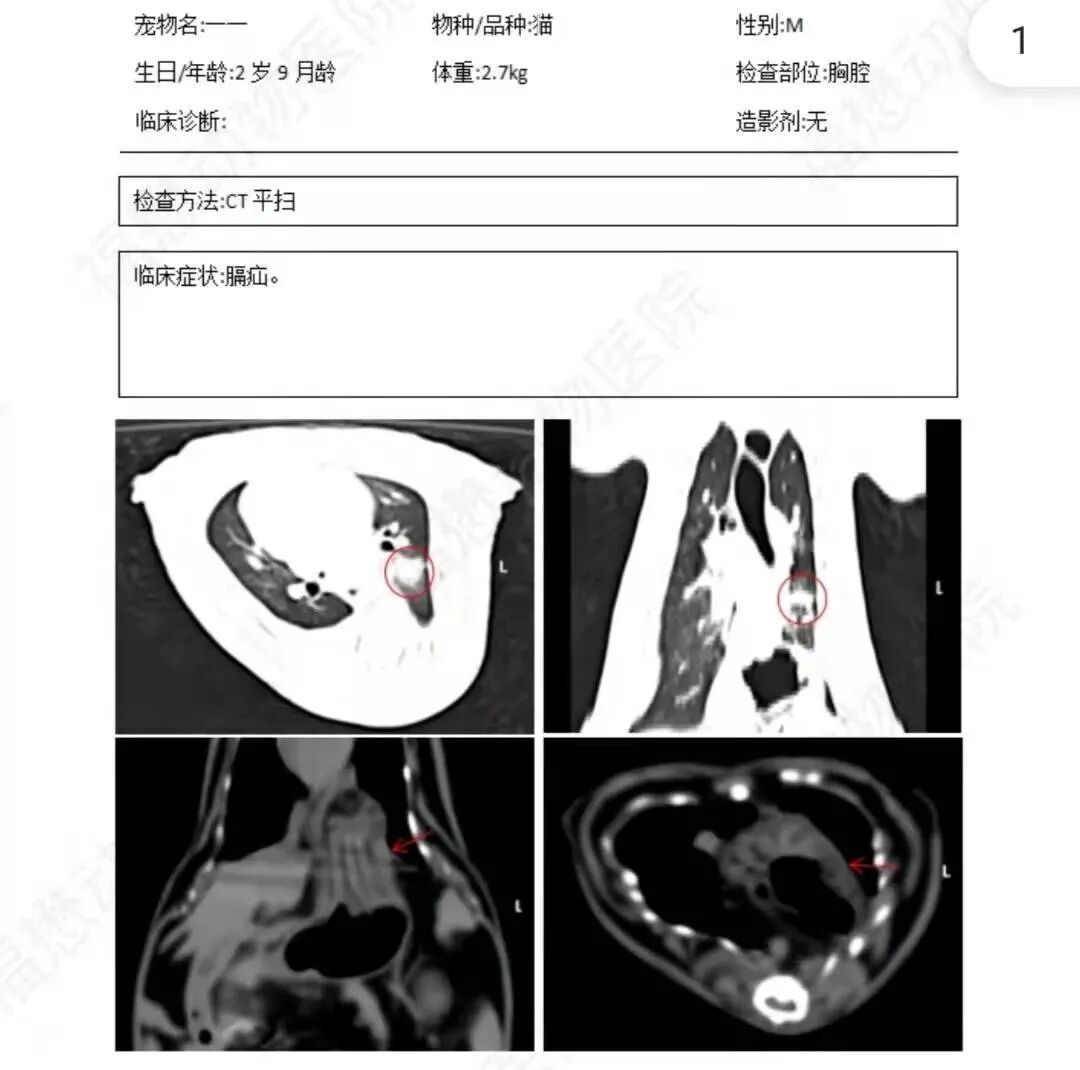

今年给我的猫咪一一治病花了8000多块。命运对一一真的很不公平,自打出生每一年都要挨一刀。最近的一次是我们带它去医院体检,发现患了膈疝——胃部有一半已经跑到了胸腔,需要做手术才能修复。

它很喜欢找我撒娇,每天下班回到家,它都会主动来找我求摸摸,在地上舒服地一边咕咕一边打滚。它第一次生病的时候,我感觉自己怎么那么倒霉,要花那么多冤枉钱在一只猫身上。现在我慢慢接受了这段命运的安排,再也不会去衡量要花多少钱才能挽救它,而是无论花多少钱都要留住它。